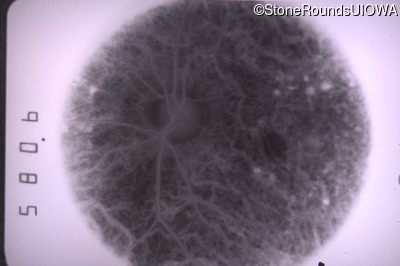

Fluorescein Angiography - Right - 20/25 sc

Exemplar

Fluorescein Angiography - Left - 20/40 -2 sc